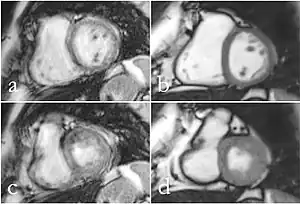

Cardiac MRI

Although applications of real-time MRI cover a broad spectrum ranging from non-medical studies of turbulent flow[26] to the noninvasive monitoring of interventional (surgical) procedures, the most important application making use of the new capabilities is cardiovascular imaging.[1] Previous cardiac MR (CMR) used cine techniques to capture the periodic motion of the heart. However, this is not feasible for patients with arrhythmia, where the cardiac cycle is unpredictable.[27] With the new method it is possible to obtain movies of the beating heart in real time with up to 50 frames per second during free breathing and without the need for a synchronization to the electrocardiogram.[28] A study performed by Laubrock et al.[27] demonstrated that RT-MRI produced higher quality images with a higher SNR than cine CMR with a bSSFP sequence and radial k-space sampling. RT-MRI also removes the need for breath-holding while imaging, leading to a more comfortable experience for the patient as well.[27]